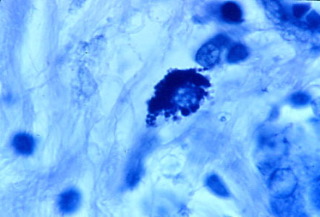

-

Fig 3

- Like bacteria observed in other forms of cancer, prostate

cancer bacteria are primarily observed in the connective tissue stroma

in tightly-packed clusters of round "coccoid" forms seemingly

embedded in a matrix. These microbes can be seen, although with difficulty,

by using the "high power" lens of the microscope, which magnifies

400 times (Figures 1 and 2). Using oil and the oil-immersion lens, which

allows magnification up to 1000 times, the organisms are seen more clearly.

The forms are primarily seen packed together in tight units in the connective

tissue stroma (Figure 3). Sometimes a cell nucleus is clearly visible in

the cluster (Figure 4). Rarely, one can see intracellular forms which suggest

short rod-shaped bacterial forms, rather than the common round coccoid

forms (Figure 5). Extracellular forms that escape from the tight bacterial

clusters can be seen scattered in the connective tissue (Figure 6). Occasionally

larger coccoid forms are seen that are three and four-times larger than

the tiniest round forms. The largest round spore-like forms seen in Figure

6 are apparently what Russell observed as his "parasite of cancer."

- Figure 3. Prostate cancer. Tightly-packed cluster of

blue and pink-stained coccoid forms in the connective tissue stroma. Fite

stain, magnification x 1000 (highest magnification), in oil.

- Figure 4. Prostate cancer. Loosely-packed intracellular

blue-stained coccoid forms. Fite stain, magnification x1000, in oil.